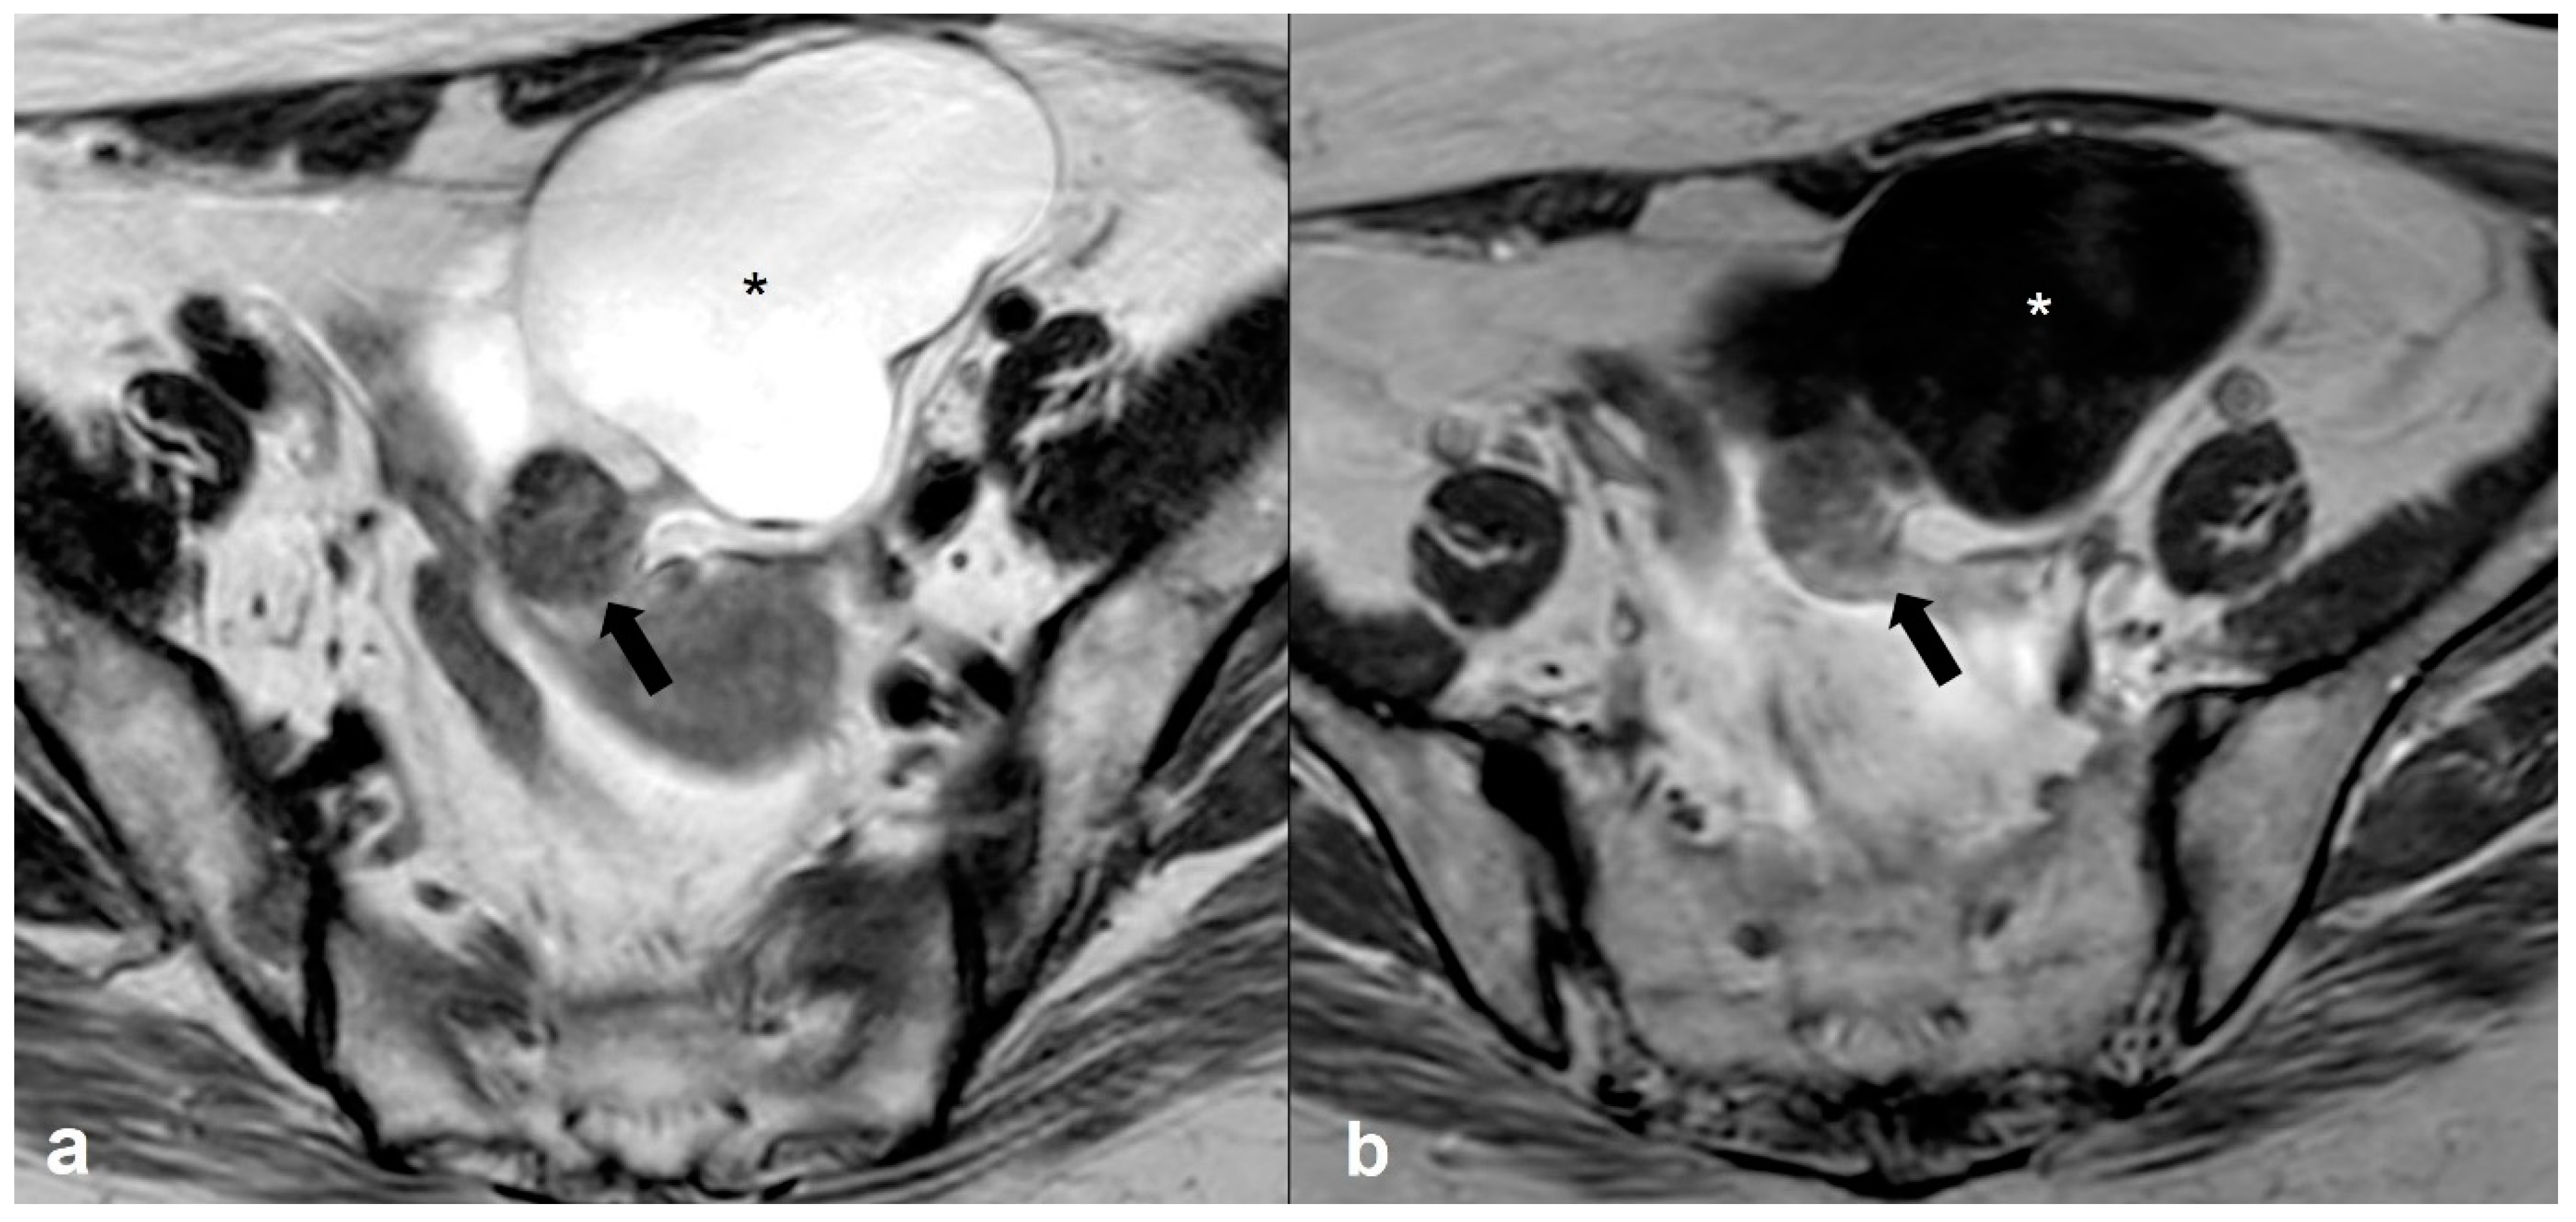

2.5.2. Decidualized Endometrioma

2.5.3. Epithelial Ovarian Cancer